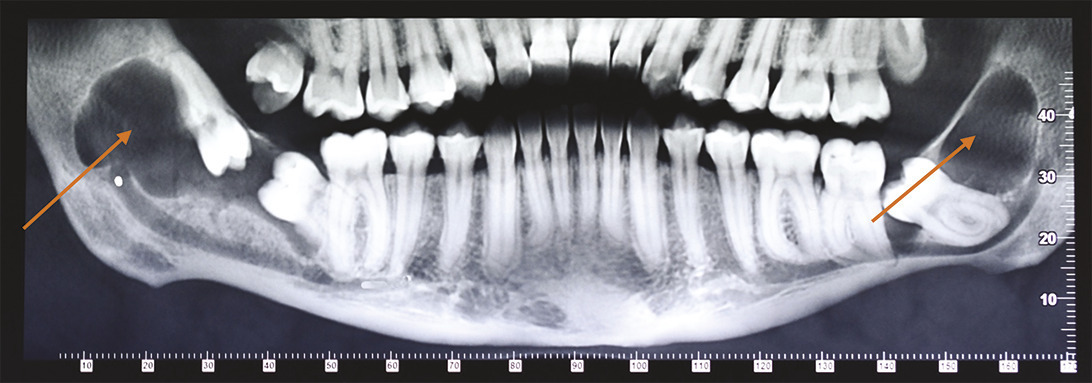

Cette femme de 26 ans consultait pour des douleurs récidivantes au niveau des dents de sagesse. Elle avait comme antécédents un asthme et une néphrectomie du rein droit en raison d’une dysplasie. Sa consommation tabagique était estimée à 6 paquets-année. Le panoramique dentaire (fig. 1 ) montrait quatre images radioclaires entourant les dents de sagesse. La patiente était alors adressée dans le service de chirurgie où un Cone Beam (fig. 2 et 3 ) permettait d’évaluer la taille des lésions kystiques ainsi que leurs rapports avec les structures anatomiques voisines. L’avulsion des dents de sagesse et l’énucléation des kystes étaient réalisées. L’examen anatomopathologique des lésions notait une paroi kystique bordée par un épithélium malpighien ortho- ou parakératosique avec une hyperplasie des couches basales compatible avec des kératokystes bénins odontogènes.

La présence simultanée de kératokystes doit faire suspecter un syndrome de Gorlin, ou nævomatose basocellulaire, maladie héréditaire transmise sur le mode autosomique dominante. Des mutations du gène PTCH1 sont responsables de ce syndrome. La pénétrance est complète mais l’expressivité variable.1 La prévalence estimée varie de 1 sur 57 000 à 1 sur 164 000. L’espérance de vie des patients atteints par ce syndrome n’est pas diminuée. La prise en charge doit être multidisciplinaire. La recherche d’un carcinome baso-cellulaire est essentielle, et l’exposition excessive aux ultraviolets est déconseillée. Les études rapportent2 par ordre d’apparition : une fibrose cardiaque chez le nouveau-né, des médulloblastomes chez le jeune enfant, les kératokystes odontogènes chez le jeune adulte et enfin les tumeurs ovariennes chez la femme en âge de procréer.